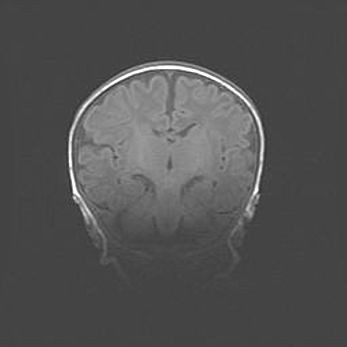

Церебральная ишемия II.

Возраст: 7 дней

Вес: 3350 г

Пол: женский

Окружность головы: 35 см

Срок гестации: 39 недель

Ишемия головного мозга – это состояние, которое развивается в ответ на кислородное голодание вследствие недостаточного мозгового кровообращения. У новорожденных она является следствием дефицита кислорода, что ведет к метаболическим расстройствам различной степени тяжести в тканях головного мозга, в том числе к развитию коагуляционных некрозов и гибели нейронов.